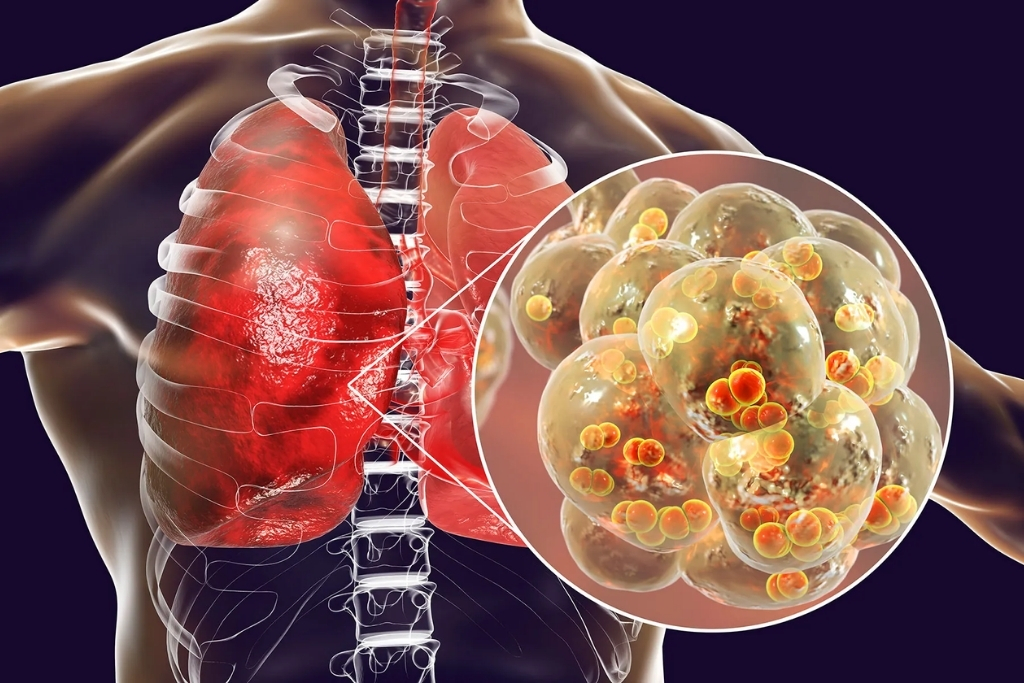

Pneumonia Treatment

Pneumonia is a lung infection that inflames the air sacs, which may fill with fluid or pus, causing cough and breathing difficulty.